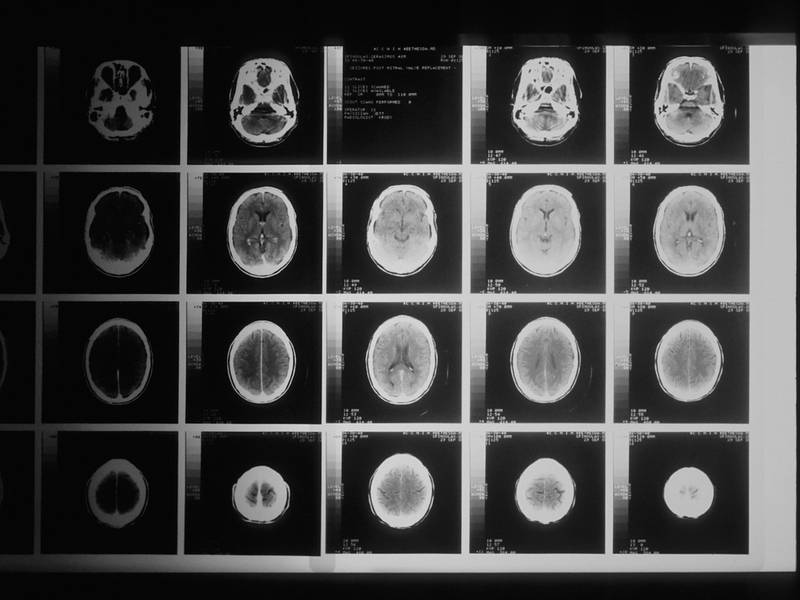

برخلاف مطالعات اپیدمیولوژیک قبلی، او به کالبدشکافی مغز بیماران در مرکز تحقیقاتی بیماری آلزایمر دانشگاه پرداخت.

او گفت: «ما رابطه نسبتا پایدار و ثابتی بین داشتن سابقه سرطان و سطوح پایینتر آسیبهای آمیلوئید در مغز پیدا کردیم که نشانه مشخص بیماری آلزایمر است.»